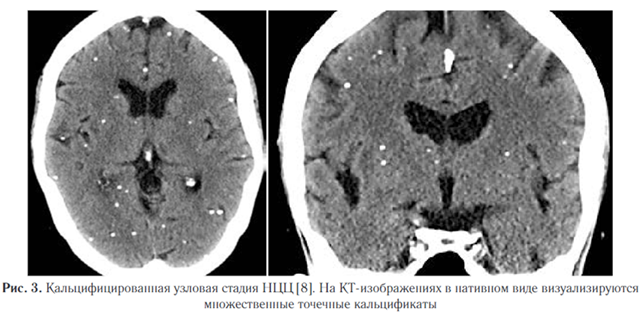

5. Кальцифицированная узловая стадия (неактивная) чаще всего проявляется в виде гранулематозного поражения, которое инволютировалось и полностью кальцинировалось (рис. 3). Нейровизуализация является очень важным методом диагностики НЦЦ в связи с тем, что позволяет визуализировать цистицерки, оценить их распространенность и локализацию в ЦНС [2]. КТ обладает высокой чувствительностью и специфичностью при большинстве форм НЦЦ и превосходит МР-визуализацию в выявлении кальцинированных гранулем. Однако внутрижелудочковые кисты могут быть трудно идентифицированы с помощью КТ из-за аналогичной плотности ликвора и жидкости кисты.